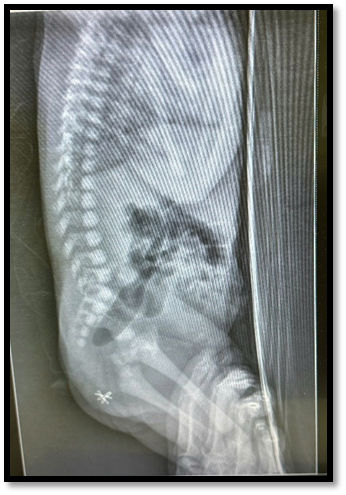

X-quang bênh nhi ngay sau sanh